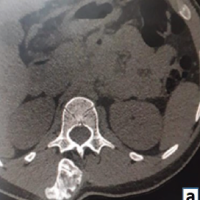

We present the case of a 35-year-old female who presented 3 weeks post-traumatic injury to her elbow. She had a fall on the flexed elbow with force directed through the olecranon tip proximally. She was initially managed with a splint in 90° elbow flexion and forearm supination. She was advised conservative management for the fracture, including immobilization for 8 weeks followed by gradual physical therapy; however, she presented to us due to constant pain and restricted elbow range. On examination, she exhibited swelling and tenderness over the medial elbow without wounds or distal neurovascular deficit. Plain radiographs of her elbow showed a half-moon-shaped fragment displaced anterosuperiorly with irregular ulnohumeral articulation in the lateral X-ray. No dislocation of the elbow joint or the radial head was noted. These findings were corroborated on subsequent computed tomography (CT) scans (Fig. 1 and 2).

Figure 2: Computed tomography scan sections showing the displaced trochlear fragment marked in a circle on (a) axial, (b) coronal, and (c) sagittal cuts.